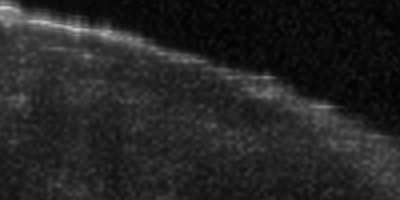

Coronary artery disease (CAD) is a cardiovascular condition with high morbidity and mortality. Intravascular optical coherence tomography (IVOCT) has been considered as an optimal imagining system for the diagnosis and treatment of CAD. Constrained by Nyquist theorem, dense sampling in IVOCT attains high resolving power to delineate cellular structures/ features. There is a trade-off between high spatial resolution and fast scanning rate for coronary imaging. In this paper, we propose a viable spectral-spatial acquisition method that down-scales the sampling process in both spectral and spatial domain while maintaining high quality in image reconstruction. The down-scaling schedule boosts data acquisition speed without any hardware modifications. Additionally, we propose a unified multi-scale reconstruction framework, namely Multiscale- Spectral-Spatial-Magnification Network (MSSMN), to resolve highly down-scaled (compressed) OCT images with flexible magnification factors. We incorporate the proposed methods into Spectral Domain OCT (SD-OCT) imaging of human coronary samples with clinical features such as stent and calcified lesions. Our experimental results demonstrate that spectral-spatial downscaled data can be better reconstructed than data that is downscaled solely in either spectral or spatial domain. Moreover, we observe better reconstruction performance using MSSMN than using existing reconstruction methods. Our acquisition method and multi-scale reconstruction framework, in combination, may allow faster SD-OCT inspection with high resolution during coronary intervention.